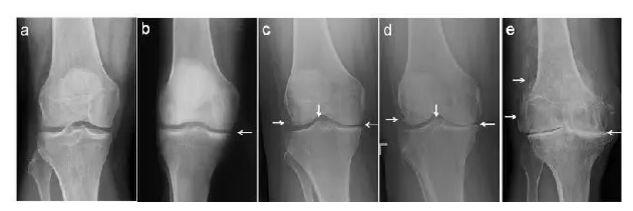

截骨矫形 部分患者可能由于下肢骨发育畸形,膝内翻或膝外翻畸形等原因导致下肢力线偏移,膝关节单侧受累,但是活动度基本正常,此时患者年龄多较小,但膝关节常存在持续性疼痛,这种情况常采用胫骨高位或股骨髁上截骨术,尽量保留膝关节,延缓膝关节退变的速度。

关节置换 对于退行性关节炎晚期,由于软骨剥脱,关节间隙变窄,关节重度退变,患者常存在持续性疼痛,甚至无法行走,此时就需要将退变磨损的关节面换掉。对于膝关节单侧受累的情况,可以选择单髁置换术,对于终末期膝关节骨关节炎全关节均已退变的患者,则需要人工全膝关节表面置换术,将膝关节完全更换为人工假体。